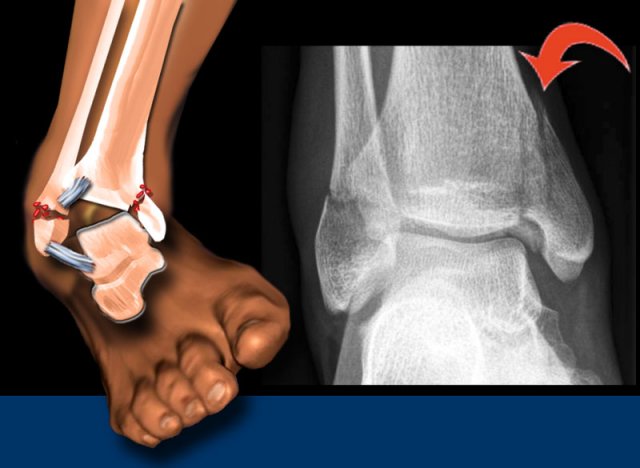

Weber A

Occurs below the syndesmosis, which is intact.

According to Lauge-Hansen, it is the result of an adduction force on the supinated foot.

• Stage 1 - Tension on the lateral collateral ligaments results in rupture of the ligaments

or avulsion of the lateral malleolus below the syndesmosis.

• Stage 2 - Oblique fracture of the medial malleolus.

Scroll through the images.

Notice that the fibular fracture is transverse, because it is an avulsion or pull-off fracture.

The tibial fracture is vertical or oblique, because it is a push-off fracture.